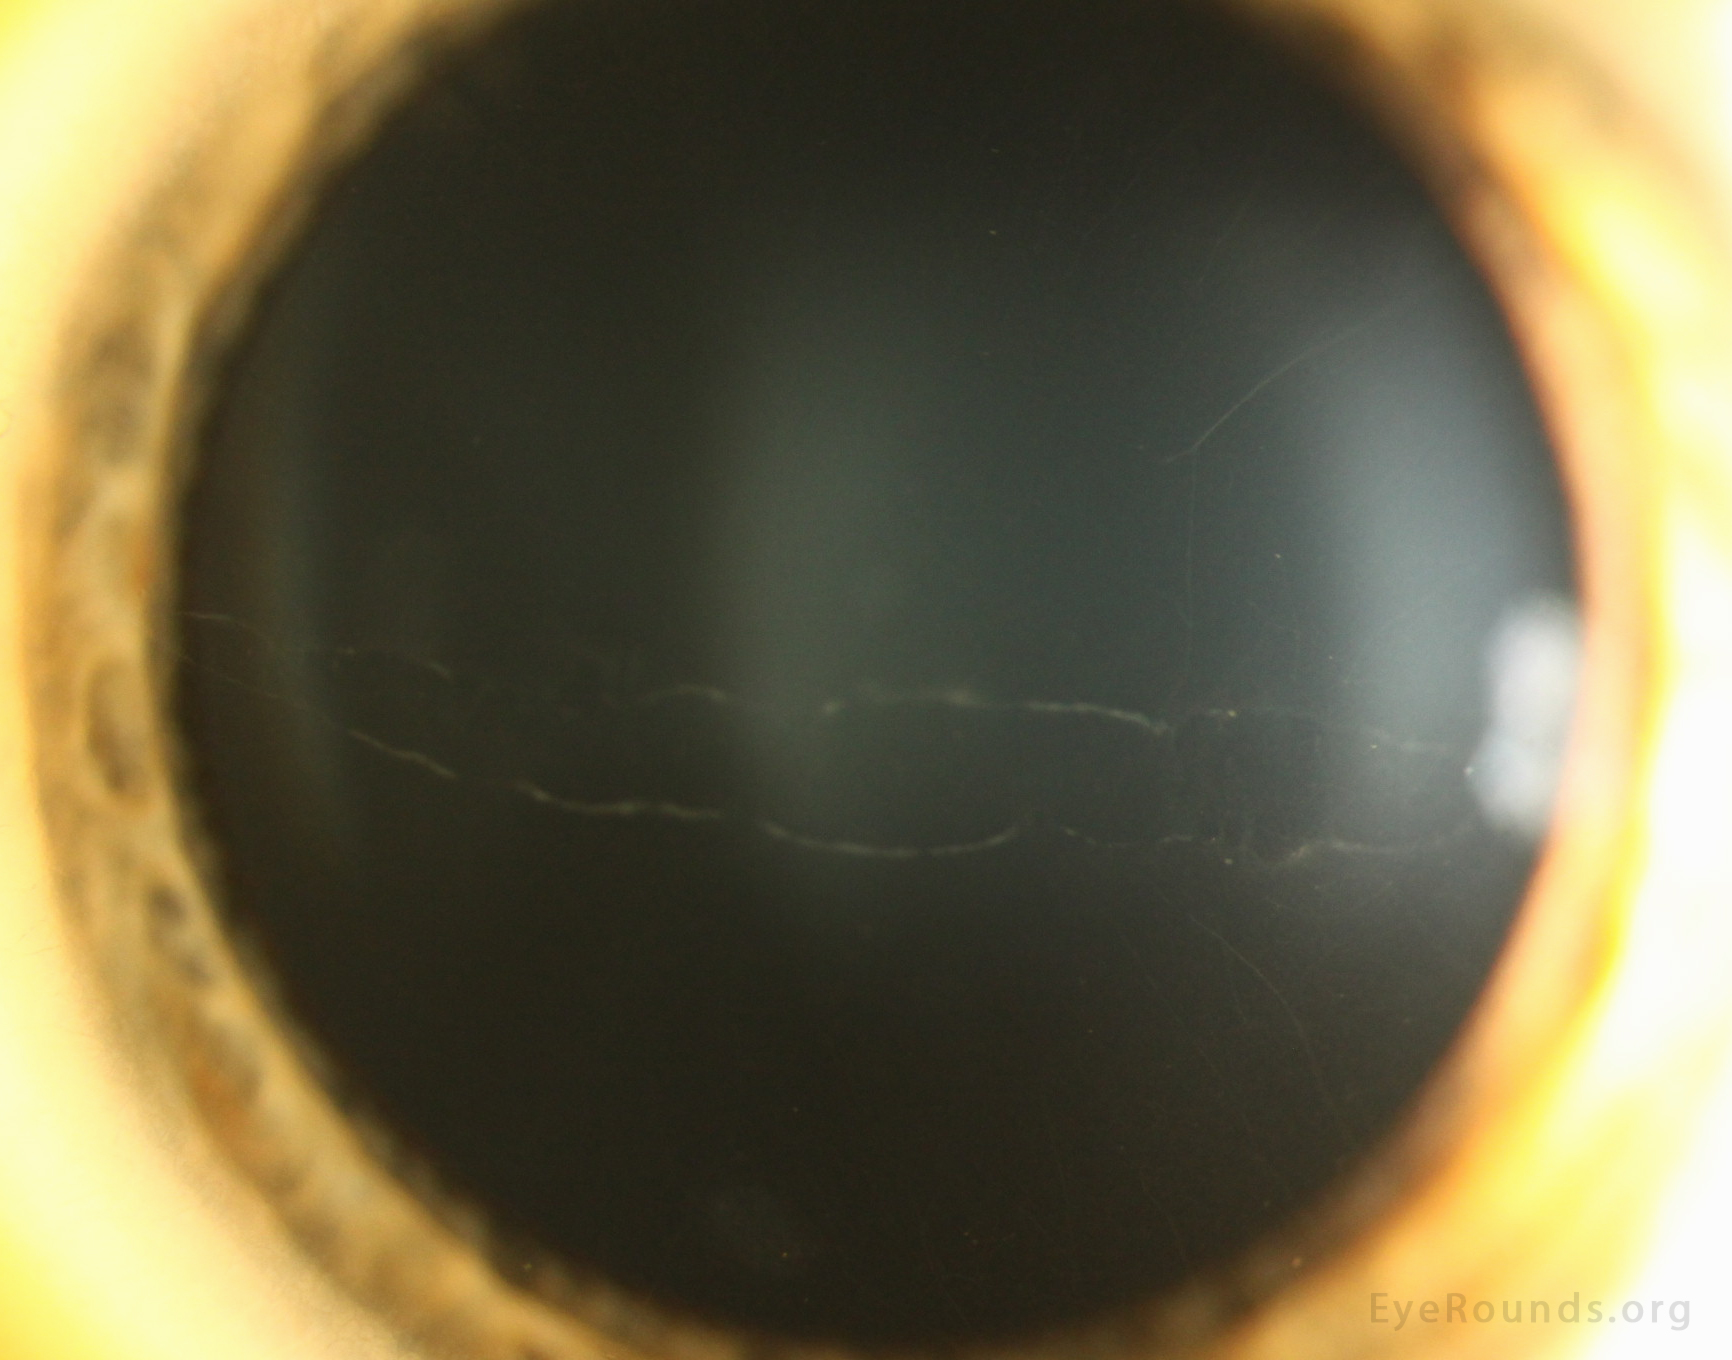

이러한 비정상적인 각막내피세포들은

각막 후면에서 희미한 회색의 소포(vesicle)이나 포진(blister)의 형태를 보이며,

선상이나 무리를 지어모여있습니다.

또한 깊은 각막 실질과 데스메막에서 증식하면서, band like thickening을 보여,

전형적인 tram track 양상을 보입니다.